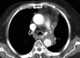

Aorticopulmonary paraganglioma